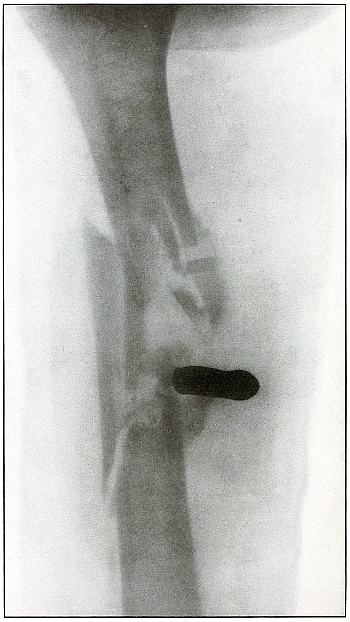

Plate 9.

[Pg 29]

Rifle—Plate 9.

UPPER EXTREMITY.

Gunshot Fracture of the Right Humerus,

with Lodgment of the Missile.

Wound of entrance, antero-external aspect of upper third of arm.

Wound of exit, none.

The missile, deformed by ricochet, struck the bone with greatly

reduced velocity and without sufficient energy to perforate the bone

by which it was deflected slightly from its course and lodged in the arm.

This is something of the same effect that might have been caused by

a shrapnel ball, under the same ballistic conditions with a normal

shrapnel velocity giving about the same penetrating force.

The wound, without infection, is in the first week or two of repair,

before any callus has formed.

Treatment is expectant.

Results favorable.